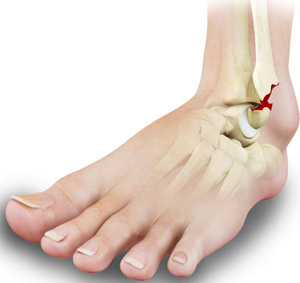

4. Stress Fractures

A stress fracture in the ankle is a small crack in the bone caused by repetitive force rather than a single injury. Athletes, military personnel, and people who suddenly increase activity levels are especially vulnerable.

Signs include:

• Stress fracture ankle symptoms that worsen with activity

• Stress fracture inside ankle

• Pain that improves with rest but returns when walking

• Pain when walking no swelling

Many people delay care because there’s no visible swelling. However, untreated stress fractures can lead to prolonged recovery times. Searches such as stress fracture in ankle recovery time, ankle brace for stress fracture, and treatment for stress fracture in ankle reflect how disruptive these injuries can be.ankle pain